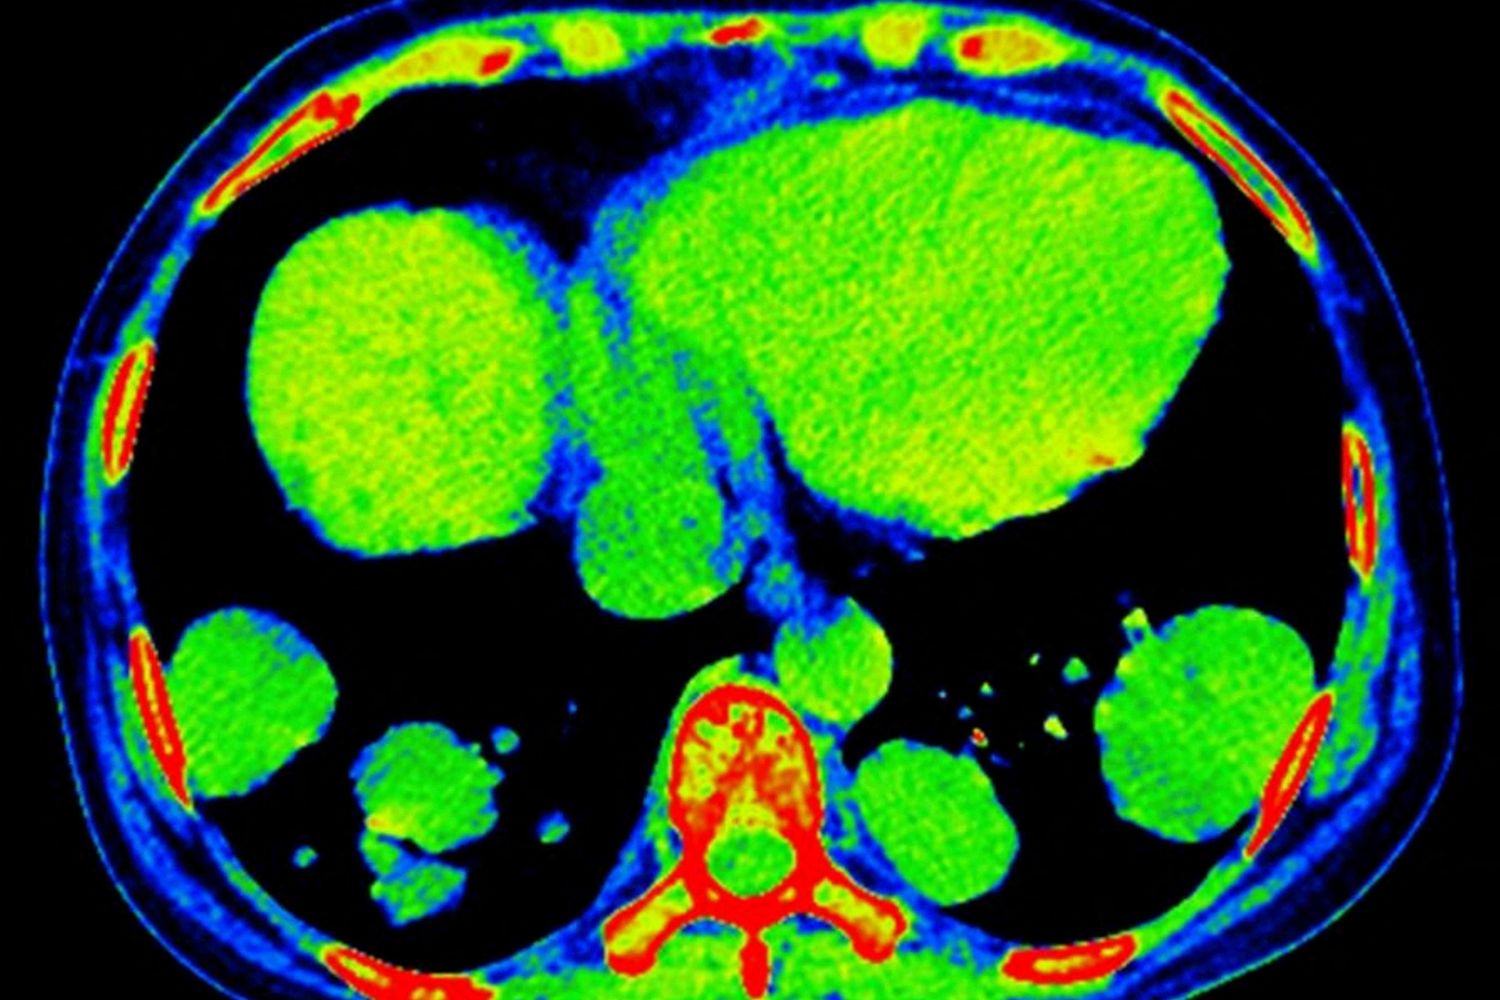

Tessuto metastatico

RAJAAISYA / SCIENCE PHOTO LIBRARY / DRH / Science Photo Library via AFP

- Tessuto metastatico